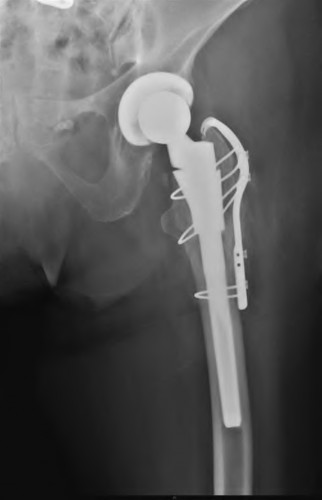

A 72-year-old male presents 2 years status post fixation of an impending pathologic right femur fracture due to metastatic renal cell carcinoma. He is minimally ambulatory due to pain. Despite radiation therapy, there has been progression of the lesion with extensive cortical bone loss, which is shown in Figure A. A proximal femoral replacement arthroplasty is performed without complications, and is demonstrated in Figure B. Which of the following is true regarding this patients post-operative course?

Deep prosthetic infection is the most common complication after hip arthroplasty performed for salvage of failed internal fixation after pathologic proximal femoral fracture secondary to malignancy.

Jacofsky et al reviewed the complications in 42 patients with a mean age of 63 who were treated with hip arthroplasty for salvage of failed treatment of a pathologic proximal femoral fracture. Multiple different constructs were used.

The most common complication was deep prosthetic infection, which occurred in nearly 10% of the patients studied. All infections occured in patients whom had previously received radiation. The mean Harris Hip score improved from 42 to 83 points post-operatively, and 41 of the 42 patients were ambulatory at follow-up. Implant survivorship free of revision for any reason at 5 years was 90%, and free of revision for aseptic failure or radiographic failure was 97%.

Figure A shows a lytic lesion of the proximal femur with an intramedullary implant. Figure B shows a proximal femoral replacement.